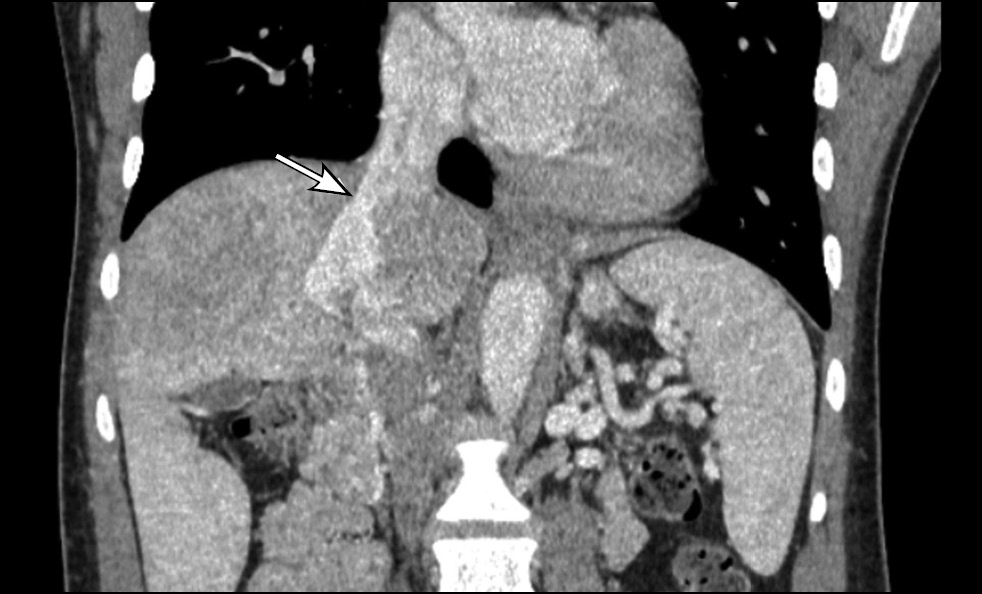

Contrast-enhanced abdominal computed tomography (CT) with multiplanar reconstruction revealed that the splenic (12 mm in diameter (Figure 1)) and superior mesenteric veins fused together, forming a portal vein conduit dilated to 28 mm in diameter (Figures 2 and 3), flowing directly into the inferior vena cava (IVC), bypassing the porta hepatis (Figure 4). Moreover, moderate liver and spleen enlargement and weak heterogeneous contrast enhancement of the liver parenchyma were noted. The findings were consistent with Abernethy malformation type Ib.

Fig. 4. Contrast-enhanced CT, portal phase, coronal view. Portal vein conduit flowing directly into the IVC (white arrow), enlarged liver with heterogeneous parenchymal enhancement.